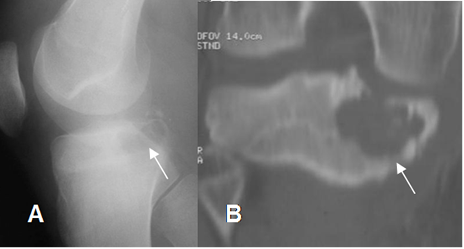

Fig 17. Lesión epifisiaria.

A: Rx AP y B: TAC reconstrucción coronal. Lesión epifisiaria, que corresponde a condroblastoma.

Fig 18. Lesión metafisiaria.

A: Rx AP y B: RM coronal en T1. Lesión metafisiaria secundaria a osteosarcoma.